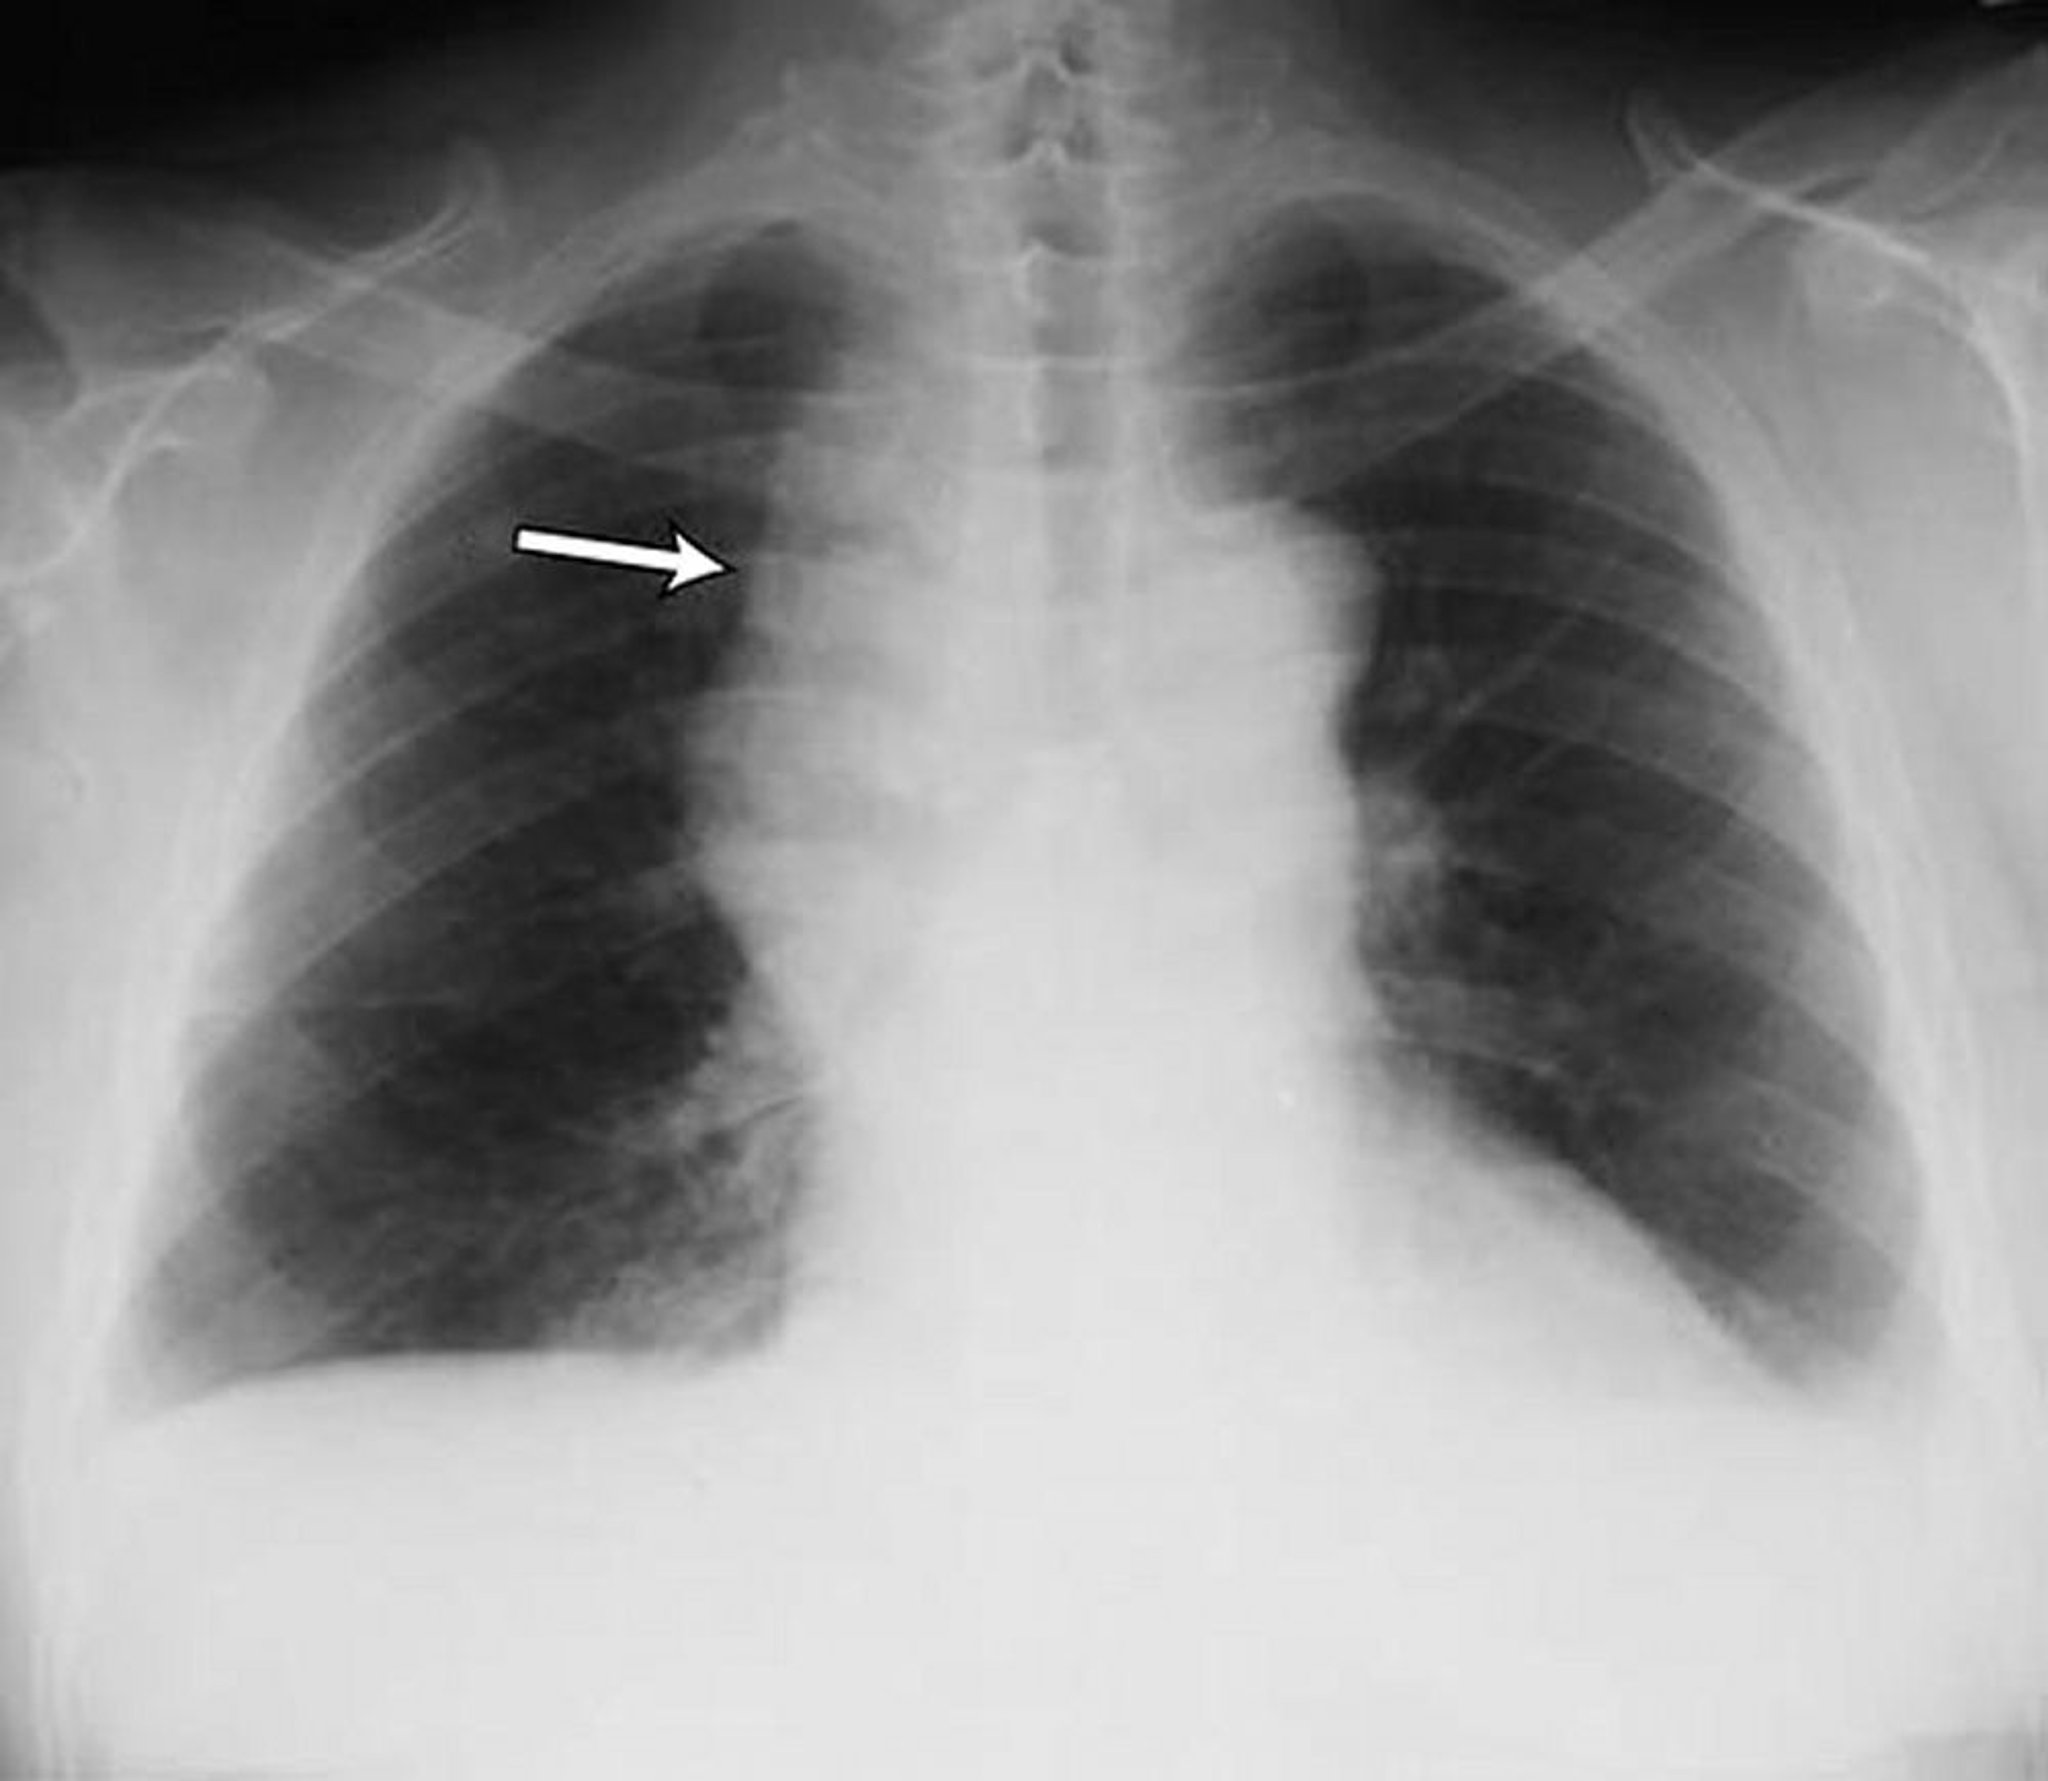

Tràn dịch màng phổi – Ít

Tràn dịch màng phổi hai bên số lượng ít ở bệnh nhân ung thư hạch không Hodgkin. Cả hai góc sườn hoành đều bị tù. Mũi tên chỉ vào trung thất rộng do u lympho.

Được sự cho phép của nhà xuất bản. Theo Huggins J, Sahn S. Trong Bone's Atlas of Pulmonary and Critical Care Medicine. Biên tập bởi J Crapo. Philadelphia, Current Medicine, 2005.